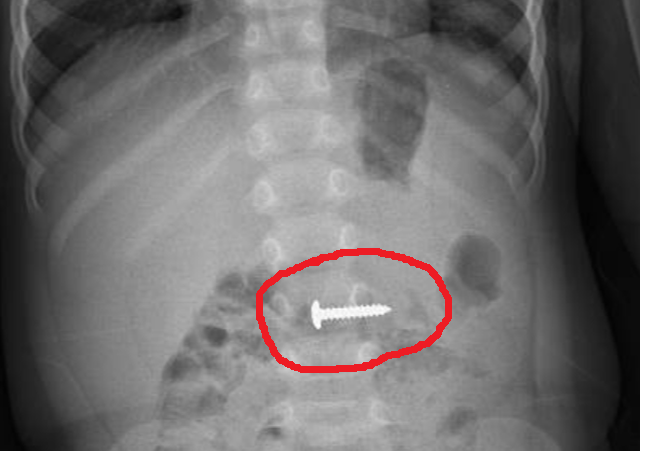

| Cây đinh vít xoắn nhọn nằm sâu trong đường tiêu hoá cháu bé. |

Tại đây, bệnh nhi được các bác sĩ khoa Ngoại Tổng hợp tiến hành khám và chỉ định chụp X-quang bụng không chuẩn bị thẳng. Kết quả phát hiện dị vật nằm trong đường tiêu hóa, có kích thước 24,15mm.